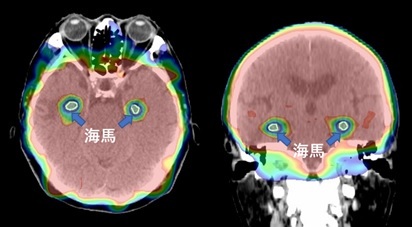

脳全体への照射では認知機能が低下することがあります。予防を目的とした線量では認知機能低下が起こる可能性は低いですが、さらに可能性を下げるため記憶を司る海馬を避けた海馬回避全脳照射を試みています(標準療法ではありません)。

小細胞がん、脳転移予防の照射。IMRTを用いて海馬を避けて脳全体に照射。

認知機能の低下を防ぎつつ脳への転移を予防できる可能性がある。